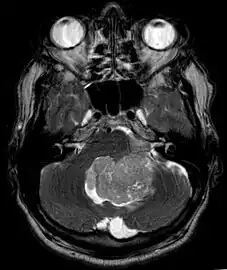

Ependymoma of 4.ventricle in MRI.

An ependymoma is a tumor that arises from the ependyma, a tissue of the central nervous system. Usually, in pediatric cases the location is intracranial, while in adults it is spinal. The common location of intracranial ependymomas is the fourth ventricle. Rarely, ependymomas can occur in the pelvic cavity.

Ependymomas make up about 5% of adult intracranial gliomas and up to 10% of childhood tumors of the central nervous system (CNS). Their occurrence seems to peak at age 5 years and then again at age 35. They develop from cells that line both the hollow cavities of the brain and the canal containing the spinal cord, but they usually arise from the floor of the fourth ventricle, situated in the lower back portion of the brain, where they may produce headache, nausea and vomiting by obstructing the flow of cerebrospinal fluid. This obstruction may also cause hydrocephalus. They may also arise in the spinal cord, conus medullaris and supratentorial locations.[4] Other symptoms can include (but are not limited to): loss of appetite, difficulty sleeping, temporary inability to distinguish colors, uncontrollable twitching, seeing vertical or horizontal lines when in bright light, and temporary memory loss. It should be remembered that these symptoms also are prevalent in many other illnesses not associated with ependymoma.